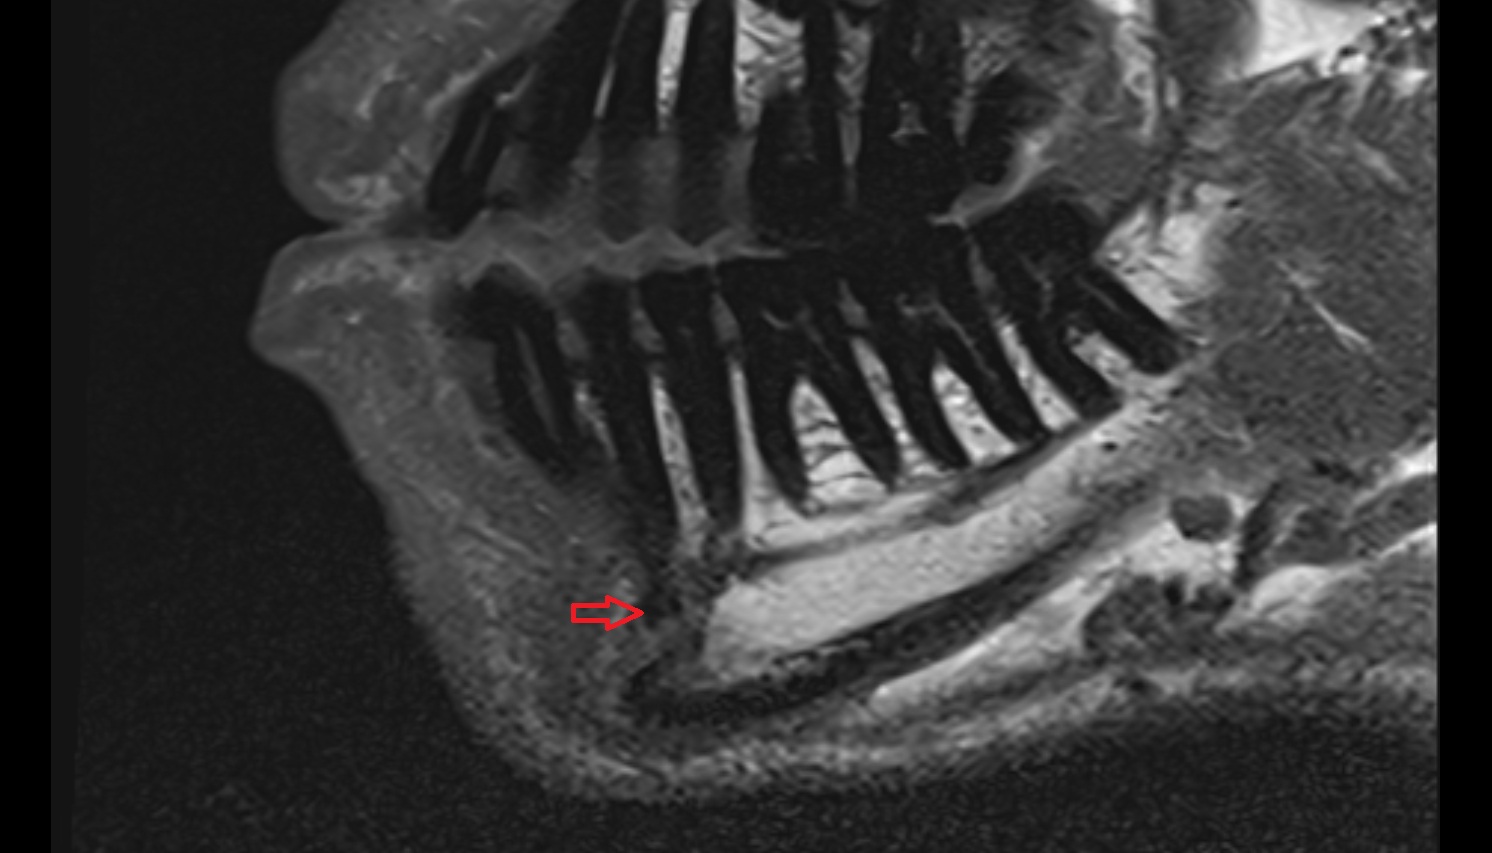

- Mandibular canal

- inferior alveolar artery

- Inferior alveolar nerve

- Mental nerve

- Inferior alveolar foramen (mandibular foramen)

- Mandibular foramen

- Root of lower molar tooth

- Lower molar apical foramen

- Mandibular nerve

- Dental branches of inferior alveolar artery, vein, & nerve